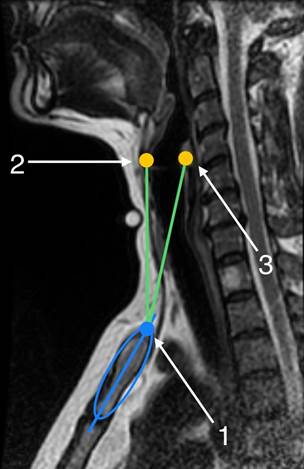

Для идентификации в сагиттальной плоскости, выбранной для навигации контрольной точки в центральной части вырезки рукоятки грудины, подбирали томографический срез, на котором размеры рукоятки грудины были наибольшими. Затем, исходя из расчета, что больший диаметр вписанной фигуры совпадал с продольной осью грудины, а меньший с линией, соединяющей наиболее удаленные точки передней и задней компактной пластинки рукоятки грудины, строили эллипс, используя соответствующий программный инструмент. Верхнюю точку пересечения диаметра и контура эллипса принимали за реперную точку на яремной вырезке рукоятки (рис. 2).

Рис. 2. Схема измерений магнитно-резонансной томограммы в сагиттальной плоскости: 1 - верхний край рукоятки грудины, соответствующий нижней точке яремной вырезки; 2 - верхний край щитовидного хряща; 3 - наиболее отдалённая назад точка дуги перстневидного хряща; синий эллипс вписан в срез рукоятки грудины в самом широком месте; синяя прямая – больший диаметр эллипса; зеленая прямая, расположенная ближе к передней поверхности шеи – отрезок от яремной вырезки до щитовидного хряща; зеленая прямая, расположенная дальше от передней поверхности шеи – отрезок от яремной вырезки до перстневидного хряща; зеленая точка – место пересечения всех отрезков

Измеряли: расстояние в продольной плоскости от реперной точки на яремной вырезке рукоятки грудины до контрольной точки на щитовидном хряще справа - расстояние в продольной плоскости; расстояние в сагиттальной плоскости от реперной точки на яремной вырезке рукоятки грудины до контрольной точки на щитовидном хряще слева - расстояние 1 в сагиттальной плоскости; расстояние в сагиттальной плоскости от реперной точки в центре яремной вырезки грудины до контрольной точки на дуге перстневидного хряща - расстояние 2 в сагиттальной плоскости 2.